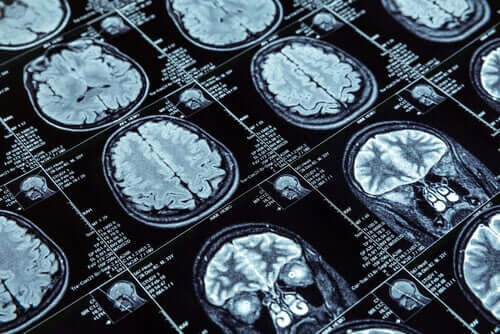

W celu przeprowadzenia badań wykonano jądrowe rezonanse magnetyczne na ponad 600 osobach, które w momencie badania obrazowego miały 45 lat. Te 600 osób było częścią większej, ponad 1000 grupy, którą Nowozelandczycy obserwowali od dzieciństwa.

W rezonansach przeprowadzonych na uczestnikach badań zmierzono grubość kory mózgowej i ilość substancji szarej u badanych. Dane te pozwoliłyby na porównanie osób o zachowaniach aspołecznych z tymi, które ich nie posiadają.

W pierwszej grupie dokonano bardzo ważnych odkryć. MRI mózgu tych osób pokazały kurczenie się kory mózgowej w porównaniu do innych, jak również nieco mniejszej ilości istoty szarej.